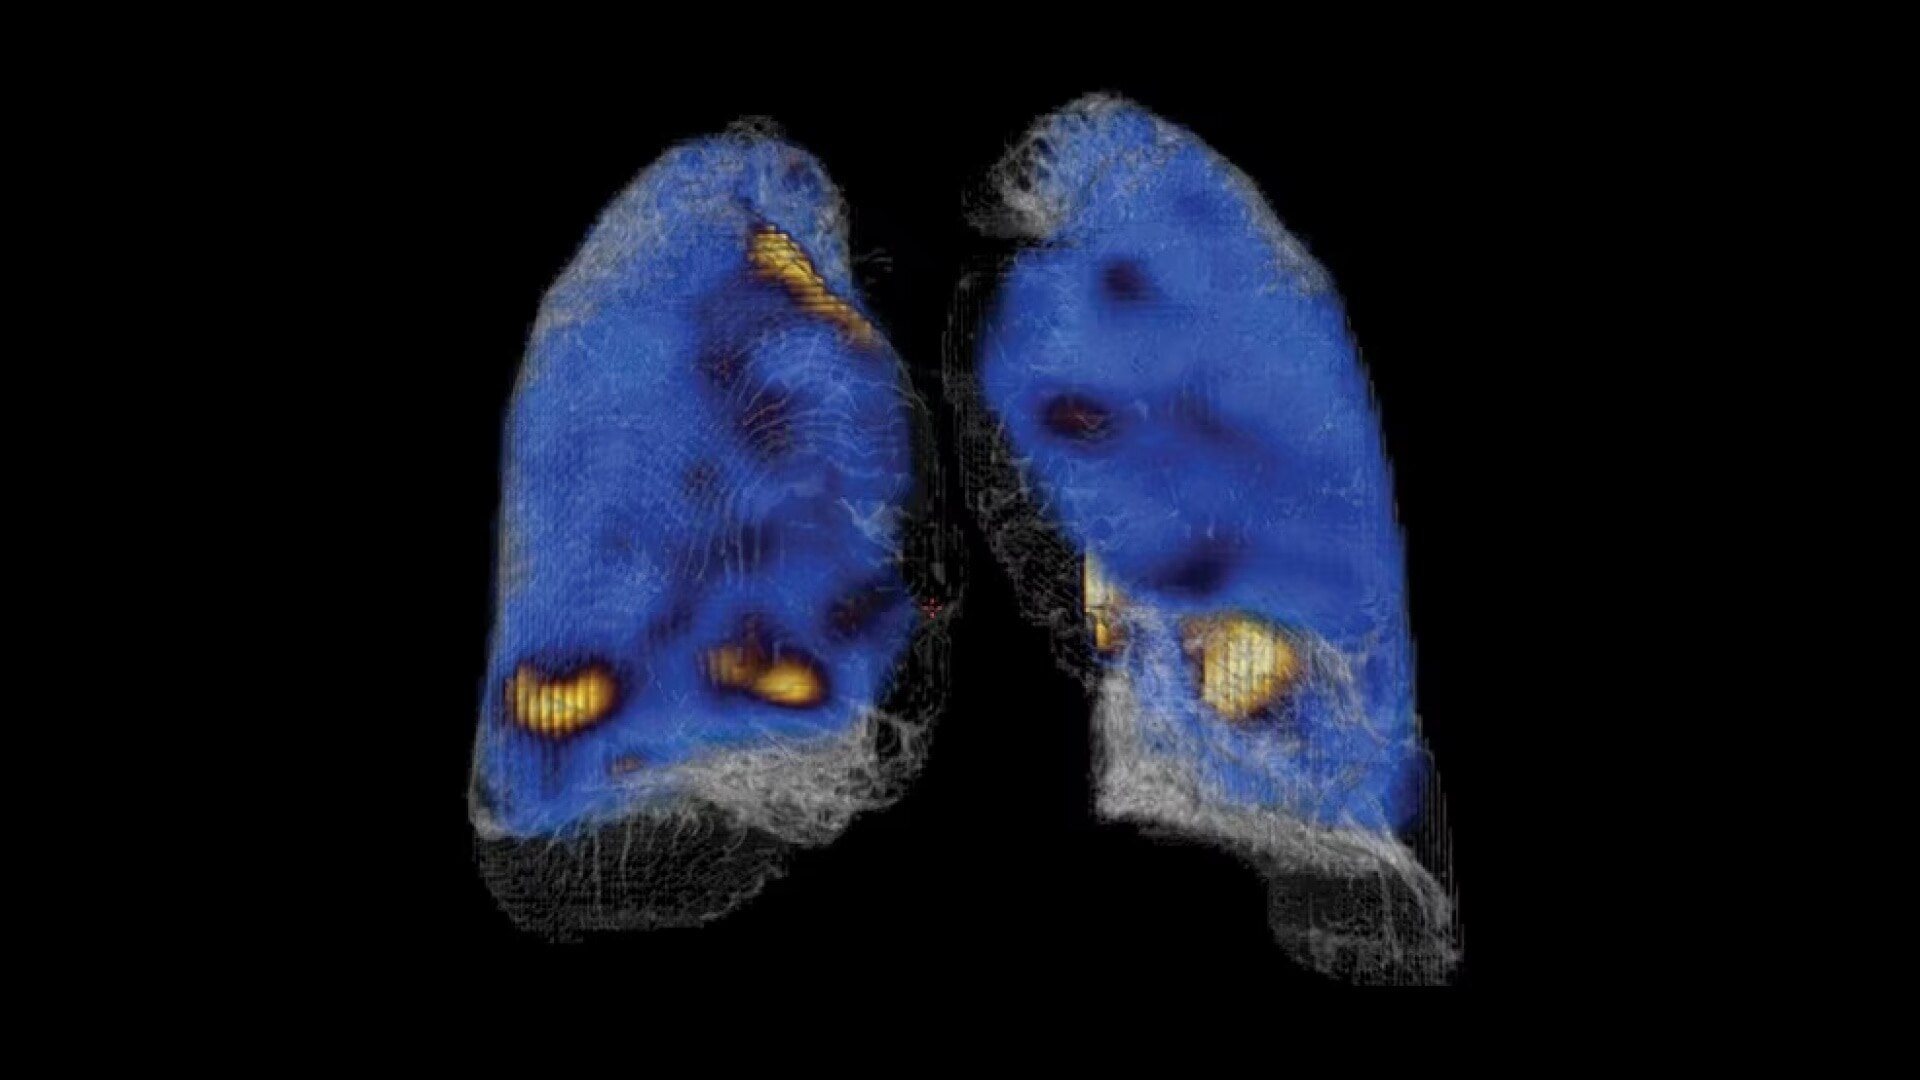

Built for quantitation

Quantitative SPECT/CT for every patient, every day

NM/CT 870 DR is a SPECT/CT built for consistent, reproducible quantitation. Improvements to detector performance enable exceptional spatial resolution for SPECT and planar images. It leverages CT-based attenuation and scatter correction along with Evolution⁴ image reconstruction. Ever-increasing computational power enables precise camera calibration for less variation between exams.

Once your quantitative studies are acquired, SmartConsole with Xeleris, makes it easier to access them - your quantitative SPECT/CT studies are automatically transferred directly to the PACS or other pre-defined DICOM destinations. An additional dataset in PET DICOM format allows you to review and evaluate images on the same devices you use to view your PET/CT studies, as adjacent information to the original SPECT/CT images.